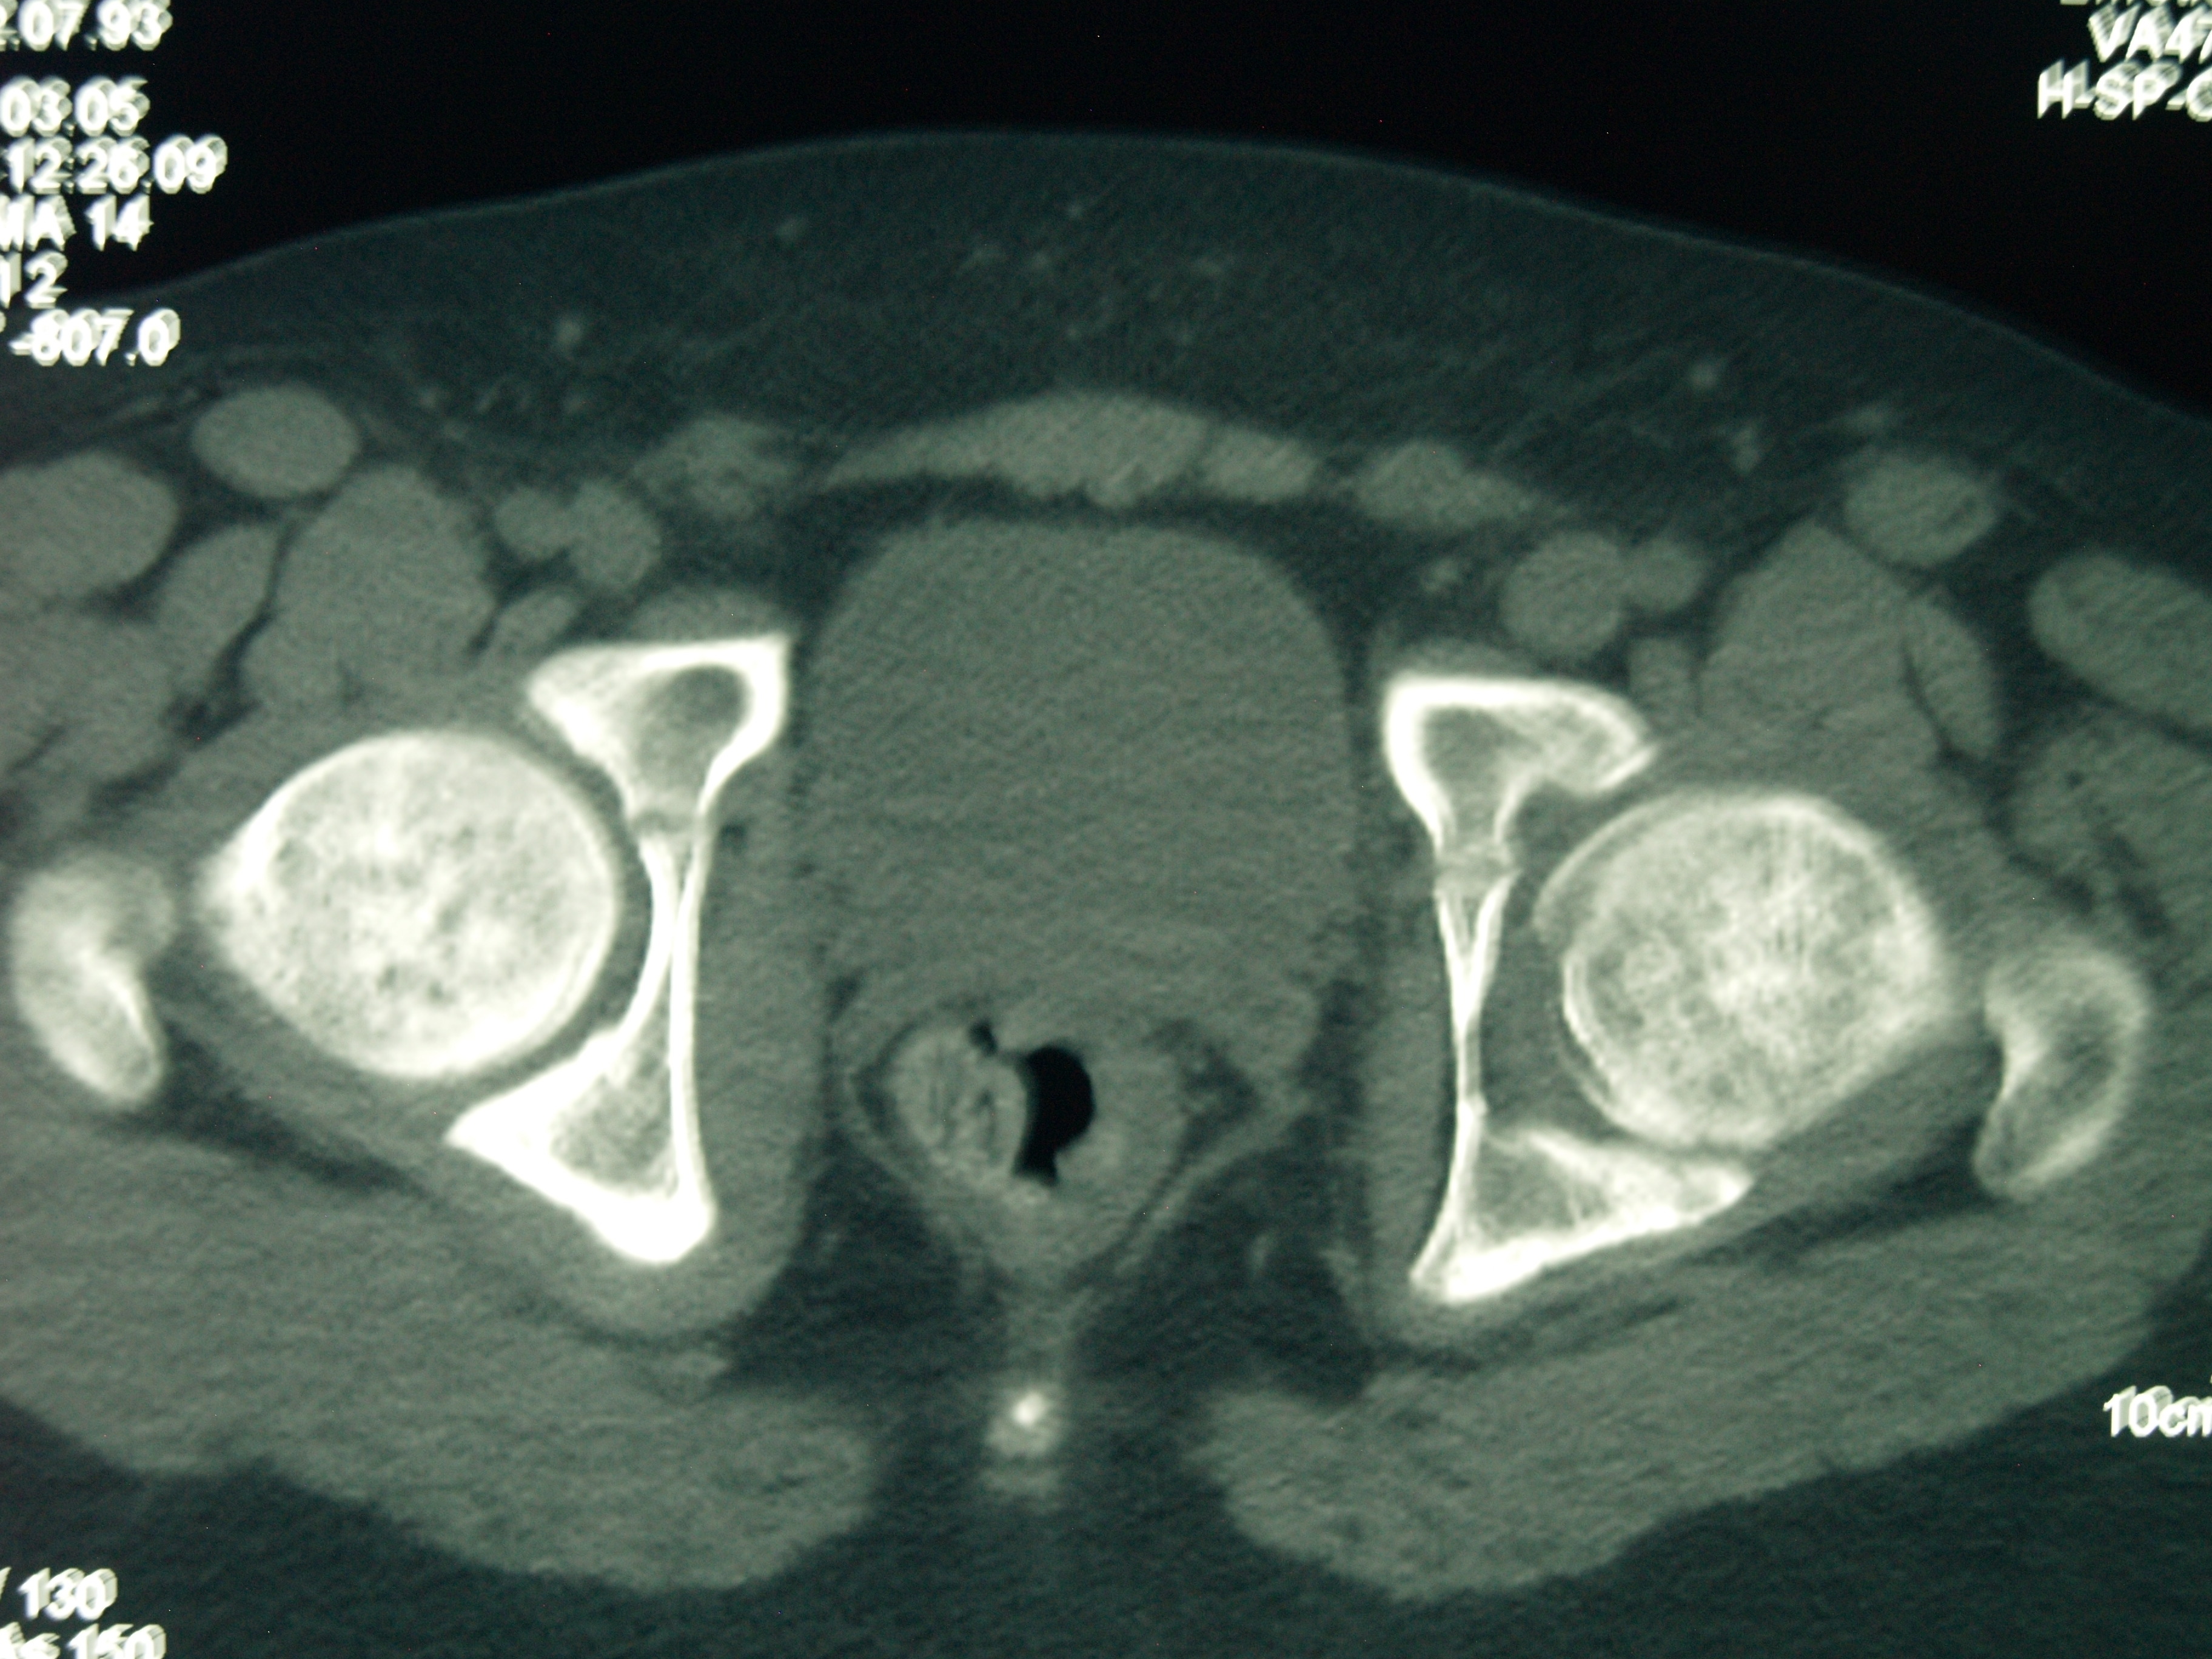

La condrolisis idiopática de cadera es una rara condición que se presenta durante la adolescencia. Se caracteriza por dolor y cojera producidos por una pérdida acelerada del cartílago articular con una disminución del grado de movilidad llegando a rigidez. La historia va desde la resolución espontánea completa a la anquilosis. El tratamiento recomendado actualmente es el conservador. Se presenta el caso clínico de un paciente de 11 años de edad con un cuadro clínico de 2 años de evolución tórpida de dolor inguinal izquierdo acompañado de cojera y rigidez. Se instauró reposo, descarga, analgésicos y rehabilitación sin mejoría inicial. Posteriormente recibió tratamiento conservador con AINE, periodos de descarga de la extremidad, tracción blanda hospitalaria, tracción ambulatoria nocturna y rehabilitación, recuperando la movilidad y marcha normal 6 años después del inicio de los síntomas. Catorce años más tarde el paciente hace una vida normal, asintomático y con movilidad simétrica de ambas caderas.